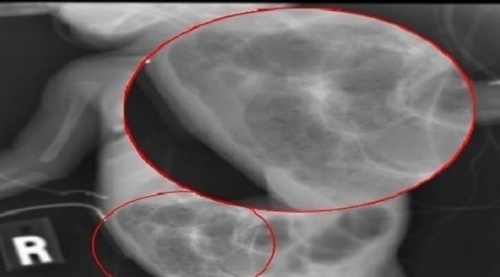

هذه الوظائف تؤثر على قلب المرأة قالت نتائج دراسة جديدة إن بعض الوظائف ترتبط بزيادة خطر إصابة المرأة بأمراض القلب، بينما تربط وظائف أ...